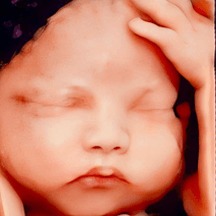

Siêu âm 4D là kỹ thuật chẩn đoán hình ảnh giúp mẹ bầu quan sát trực tiếp hình ảnh và hoạt động của thai nhi trong bụng mẹ. Hình thức siêu âm này mang đến xúc cảm chân thực cho ba mẹ vì cảm giác như con đang ở ngay cạnh mình vậy✅ Siêu âm 4D còn giúp phát h